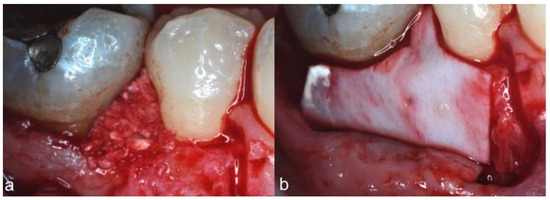

2. Case Series

2.3. Therapeutic Intervention